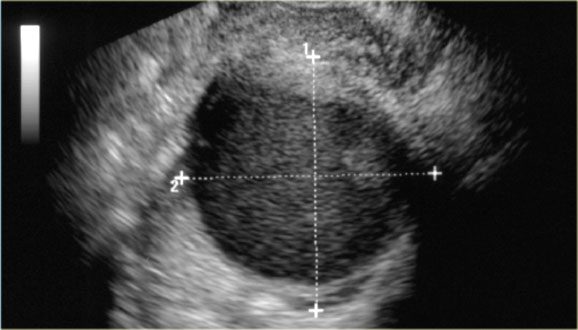

Vaginal ultrasound showing a large hypoechoic cystic lesion with diffuse low-level echo's Vaginal ultrasound showing a large hypoechoic cystic lesion with diffuse low-level echo's

Endometrioma

On ultrasound endometrioma can be variable but the great majority (about 95%) of patients present with a classic homogeneous, hypoechoic cyst with diffuse low level echoes.

Rarely it is anechoic, mimicking a functional ovarian cyst.

Endometriomas can be multilocular and have thin or even thick septations.